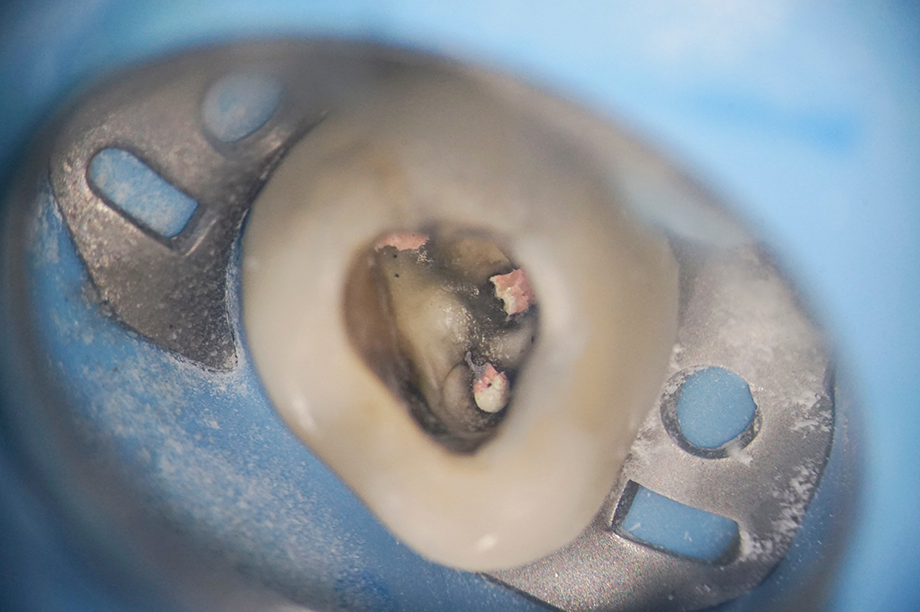

マイクロスコープ(歯科用顕微鏡)

暗く細い根管内を20倍に可視化

根管(歯の神経が入っている管)の太さは、わずかコンマ数ミリです。

これまでは歯科医師の「手先の感覚」に頼る部分が大きかったのですが、マイクロスコープにより、暗い根管の底まで明るく照らし、20倍以上に拡大して観察できます。

肉眼では絶対に見えない「隠れた根管」や、再発の原因となる「古い薬剤の残り」、微細な「歯のひび(破折)」を発見できるため、格段に診断と治療の精度が上がります。